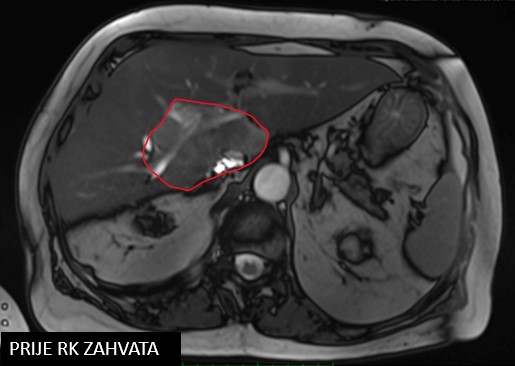

Npl. Hepatis/ Npl. Cholangiocellulare vrs.

SBRT npl hepatis (07/2018)

SABR meta hepatis (12/2019)

Rezultat – 15 mjeseci nakon RK

Regresija tretirane lezije za 47%